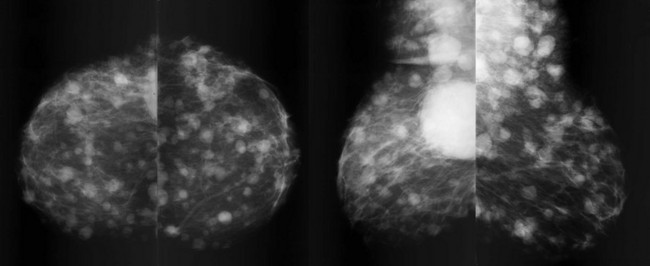

Metastatic lesions in the breast are usually a late finding of malignancy. They typically present as multiple round bilateral breast masses (Fig. 11-17), and may also be present in the subcutaneous tissues of the axilla. The mass margins are usually ill-defined compared with those of multiple cysts or fibroadenomas. Metastasis can also present as axillary or intramammary adenopathy (Fig. 11-18).

FIGURE 11-17 Metastatic Lung Carcinoma.

Multiple bilateral masses are present, including in the subcutaneous fat of the axilla. The margins of the masses are ill-defined. This mammographic appearance should not be confused with multiple benign masses, which are discussed in Chapter 8, Multiple Masses. (Reprinted with permission from Harvey JA. Unusual breast cancers: Useful clues to expanding the differential diagnosis. Radiology 2007;242:683-694.)